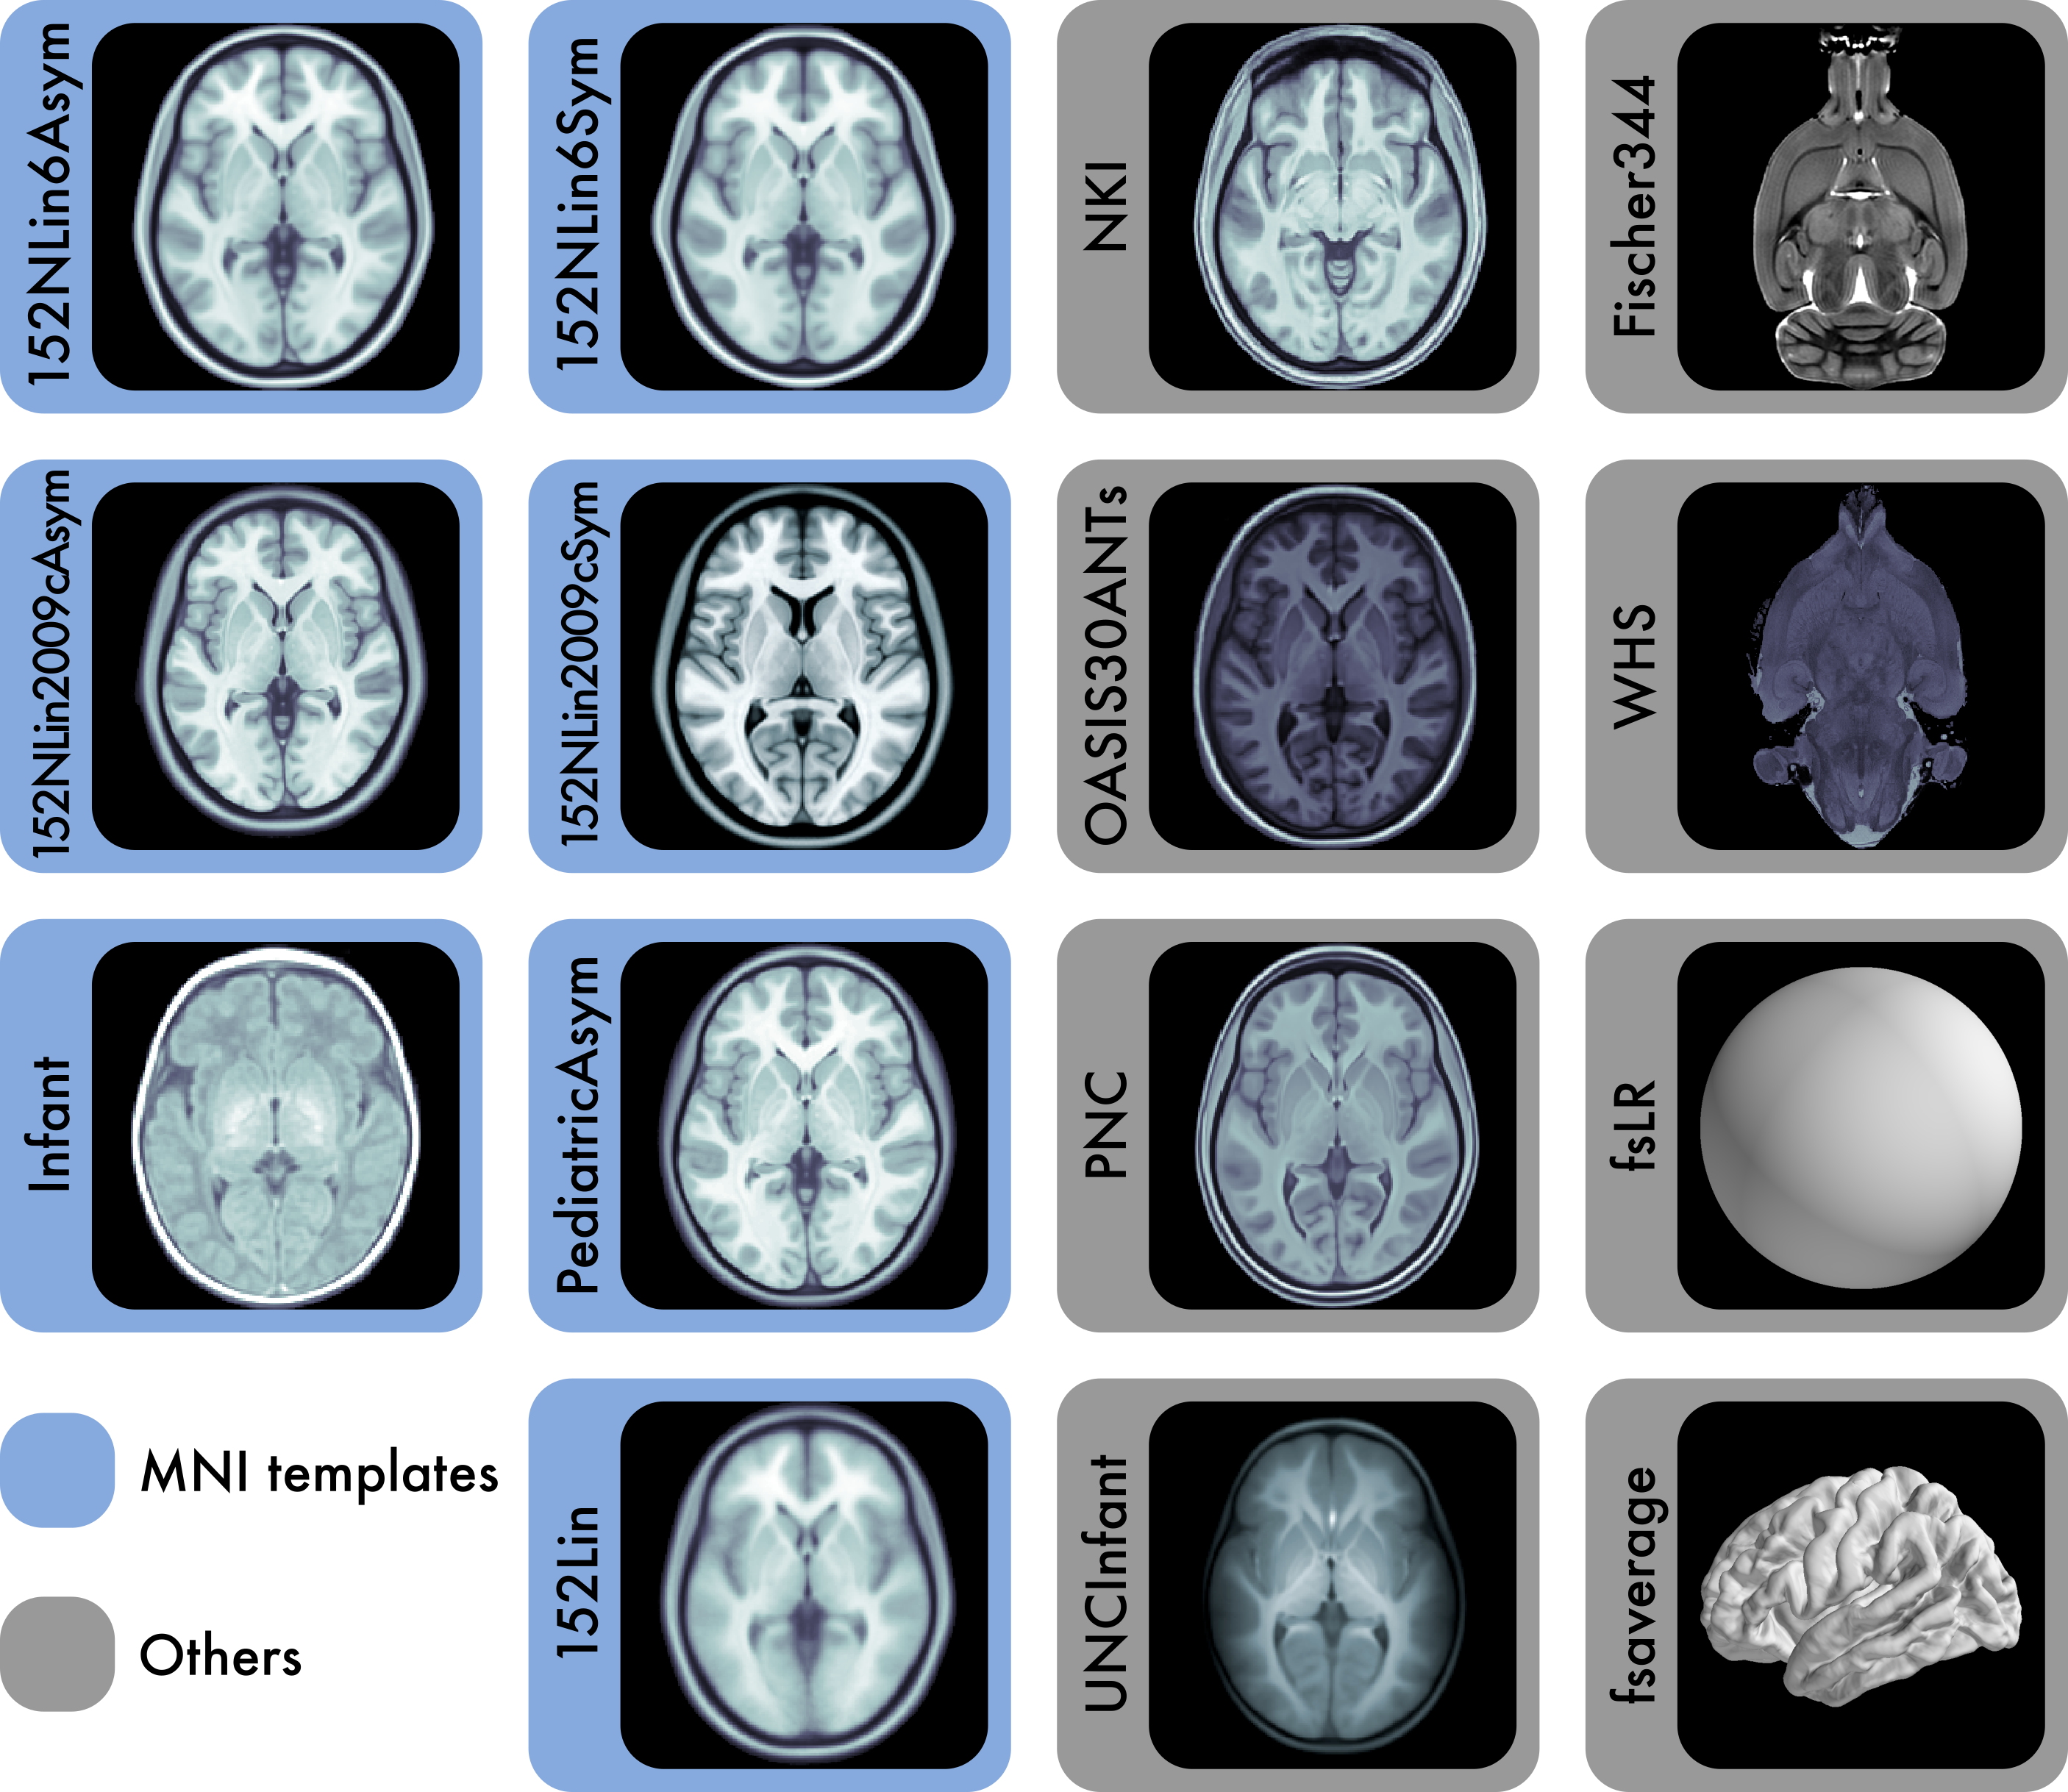

Reference anatomies of the brain and corresponding atlases play a central role in experimental neuroimaging workflows and are the foundation for reporting standardized results. The choice of such references —i.e., templates— and atlases is one relevant source of methodological variability across studies, which has recently been brought to attention as an important challenge to reproducibility in neuroscience. TemplateFlow is a publicly available framework for human and nonhuman brain models. The framework combines an open database with software for access, management, and vetting, allowing scientists to distribute their resources under FAIR —findable, accessible, interoperable, reusable— principles. TemplateFlow supports a multifaceted insight into brains across species and enables multiverse analyses testing whether results generalize across standard references, scales, and in the long term, species, thereby contributing to increasing the reliability of neuroimaging results.